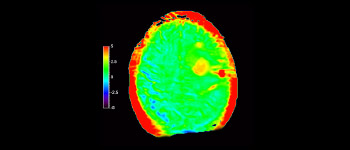

Brain lesion

with 3D APT

3D APT (Amide Proton Transfer) is a unique, contrast-free, brain MR imaging method addressing the need for more confident diagnosis in neuro oncology. 3D APT uses the presence of endogenous cellular proteins, to produce an MR signal that directly correlates with cell proliferation, a marker of tumoral activity. 3D APT can support trained medical professionals in differentiating low grade from high grade gliomas and, in differentiating tumor progression from treatment effect1.